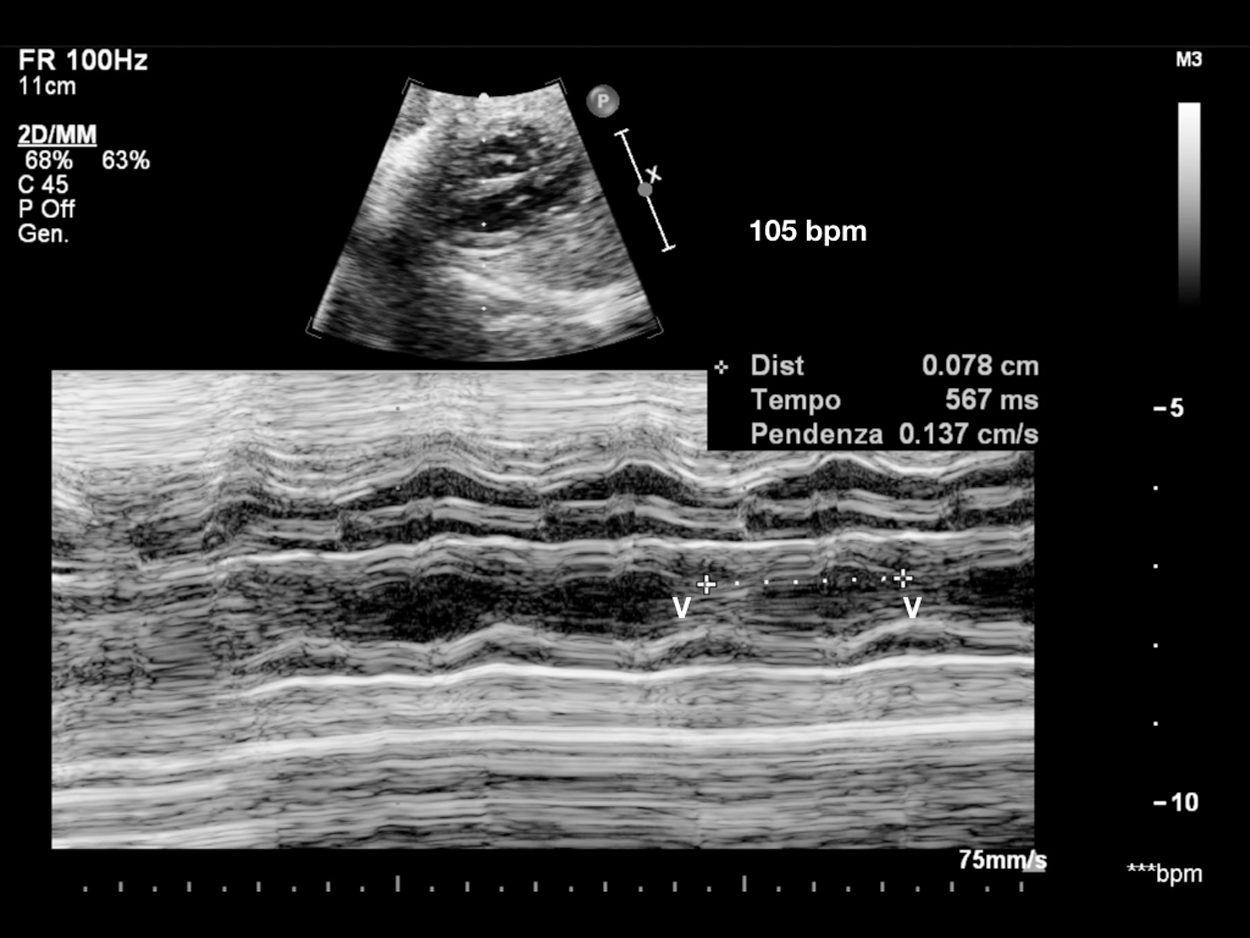

Figure 1: Sinus bradycardia. V-V interval 567 msec in patient with LQTS syndrome at birth. Consanguineous couple, both carriers of KCNQ1 and LAMC2 heterozygous mutations (epidermolysis bullosa). Two previous sons died, one at 14 months of S. Jervell-Langel-Nielsen (S. JLN), and one at 1 month of Epidermolysis bullosa. Third pregnancy amniocentesis: heterozygous KCNQ1 mutation (S. of JLN, LQT1). V = ventricle

Sinus bradycardia shows regular intervals between ventricular contractions (V-V interval) measured by M-mode or Doppler recordings through which accurate assessment of the pattern of atrial activity (regular or irregular A-A interval) and the temporal relationship between each atrial and ventricular activity (AV interval) can be performed. This analysis is defined as “the cornerstone” that allows correct diagnosis of any form of arrhythmia’s underlying electrophysiological mechanism. When the A-A intervals have little different lengths (Fig. 11), it needs to measure the A-A intervals over a period of time and the AV interval for each cardiac cycle. Five to 10 cardiac cycles are usually sufficient to evaluate the electrophysiological mechanism, but it is recommended to repeat various assessments to confirm diagnosis [2].